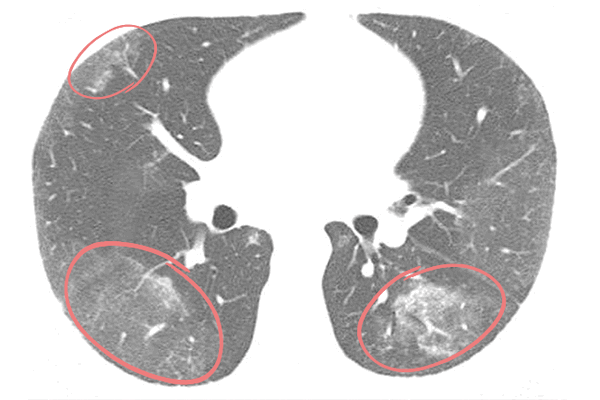

Оценивая данные КТ легких, врач-рентгенолог дифференцирует заболевания по специфической картине «матовых стекол»: их количеству, локализации, наличию других признаков, по которым возможно определить причину патологических изменений ткани легких. Например, для двусторонней вирусной пневмонии характерно наличие «матовых стекол», расположенных периферически в нижних и задних отделах легких. В более поздней стадии наблюдается консолидация очагов инфильтрации с утолщением перегородок альвеол.

Для пневмонии, вызванной коронавирусом COVID-19, характерно периферическое расположение очагов поражения под плеврой. Наиболее уязвимы билатеральные нижние доли и задние отделы легких. Отмечается тенденция к консолидации «матовых стекол» и утолщению перегородок альвеол, иногда — признаки фиброза легких.